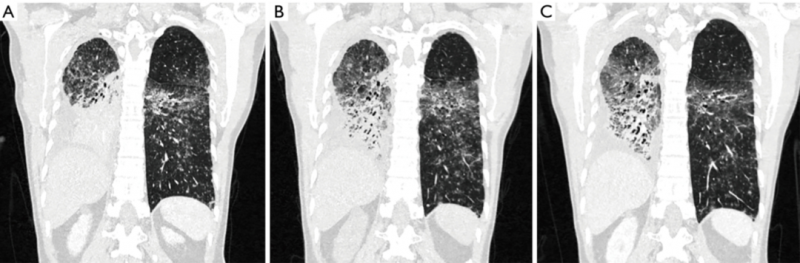

张大爷再一次幸运的参加了伏美替尼的临床试验。让张大爷没想到的是,这款药物的效果比第一次接受的TAK788还要好,仅3个月,他就达到了部分缓解,这意味着他的肿瘤病灶至少缩小了30%!下面这张治疗前后的CT也清晰的展示了病灶的缩小。并且截止到2022年3月文献发表时,张大爷仍在接受治疗,伏美替尼给张大爷带来了持久的缓解,我们也希望张大爷能继续获益于伏美替尼的治疗,也希望一代一代的靶向药能层出不穷,让病友们都能活过5年,10年!